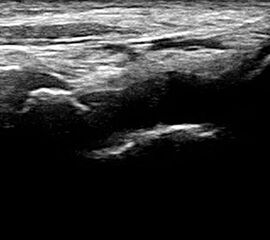

Dorsaler TS hinter dem Innenknöchel.

Abbildung 46

Lagerung: Rückenlage, Außendrehung des Beines.

Schnittführung: TS und LS hinter dem Innenknöchel beginnen und bis zum Os cuneiforme mediale fortführen.

Referenzstrukturen: Innenknöchel, Talus, Os naviculare, Os cuneiforme mediale, Sehnen der Mm tibialis posterior, flexor hallucis longus, flexor digitorum.

Befunde: Häufig betreffen die Pathologen die Tibialis-posterior-Sehne, die als erste Sehne hinter dem Innenknöchel zur Darstellung kommt. Halo-Phänomen und echoarme Verdickung bei akuter Tendinopathie, zunehmend inhomogen und echogen mit Kaliberschwankungen bis hin zu Teilrupturen bei Chronifizierung 5. Für die Erkennung von Teilrupturen sind TS in verschiedener Höhe besonders wichtig. Bei komplettem Riss mit Retraktion im LS Bild wie Spargelspitze mit umgebender Flüssigkeit oder Hämatom. Ein Os tibiale externum erscheint als echoreiche Struktur im Verlauf der Tibialis posterior Sehne mit dorsaler Schallauslöschung. Ein Os naviculare cornutum imponiert als starke Prominenz im Ansatzbereich der Tibialis posterior Sehne.